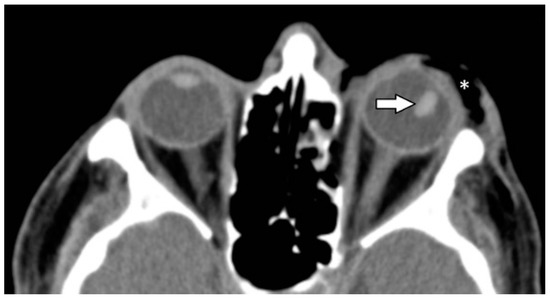

| Ocular globe and lens | 38 (37.6) | |

| Deformed globe or vitreous body | 24 (23.8) | |

| rupture of ocular globe | 7 (6.9) | |